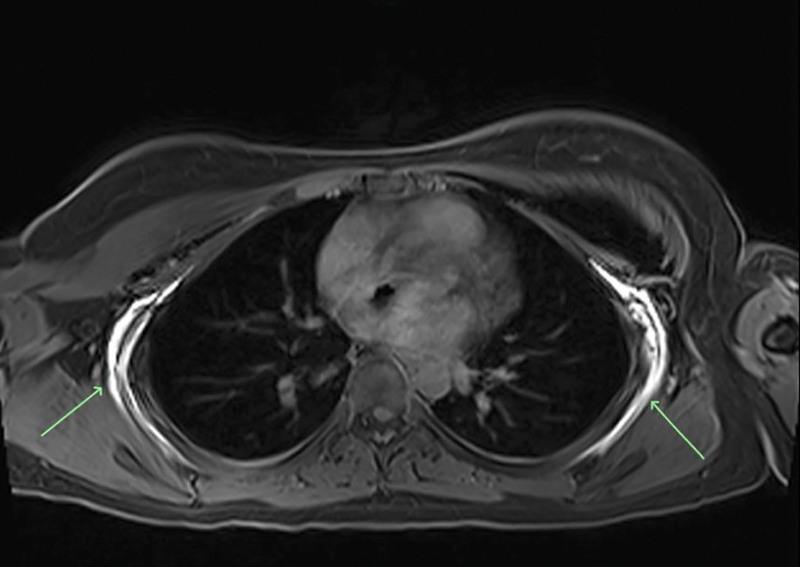

https://cdn.ncbi.nlm.nih.gov/pmc/blobs/ed06/9584193/67058ecc1045/gox-10-e4584-g001.jpg